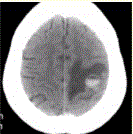

问题 患者女,55岁,右侧肢体无力3d。头颅CT显示如下图。 根据CT表现,可能的诊断为

选项 A.急性脑血肿 B.转移瘤伴出血 C.胶质瘤伴出血 D.少枝胶质细胞瘤伴出血 E.血液系统病变伴脑出血 F.脑脓肿 G.血管畸形伴出血

答案 ABCEG